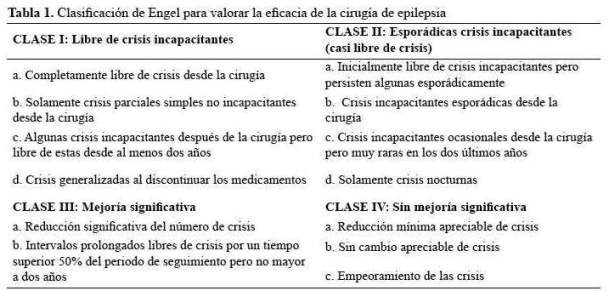

Estudio descriptivo, retrospectivo de una serie de casos, de pacientes adultos con epilepsia focal lesional farmacorresistentes operados en el Hospital Rebagliati de EsSalud de Lima – Perú. Se revisó la base de datos de La Unidad de Epilepsia de Adultos del Hospital Rebagliati, desde enero del 2012 hasta octubre del 2016. En EsSalud, se atienden en los servicios de adultos a todos los pacientes mayores a 15 años. Se seleccionaron todos lospacientes con epilepsia focal lesional farmacorresistente, en quienes se realizó cirugía resectiva de epilepsia. Se obtuvo información de cada paciente de dicha base de datos y de sus respectivas historias clínicas para evaluar las características demográficas, clínicas, electrográficas, de neuroimágenes y características respecto a la eficacia, seguridad, complicaciones de la cirugía de epilepsia. La eficacia se valoró mediante la escala de Engel (tabla 1), ampliamente difundida y utilizada en múltiples estudios previos (11 -16). Para el análisis de resultados, empleamos estadística descriptiva.

El tiempo de seguimiento fluctuó entre 5 a 32 meses, con una media de 19,4 meses.Los resultados de eficacia quirúrgica fueron de libertad de crisis (Engel I) en los 5 pacientes al término de seguimiento. Cabe mencionar que la paciente 1, a los 18 meses de la cirugía planificaba gestación y por cuenta propia redujo gradualmente su medicación: Carbamazepina 1200 mg/ día a 200 mg/día y luego de 3 semanas presentó auras de miedo menores a 30 segundos sin otra fenomenología, 2 a 3 veces/semana por 2 semanas no siendo incapacitantes; se logró revertir tal situación al instaurar tratamiento antiepiléptico con Levetiracetam 2 g/día con titulación rápida (la paciente no aceptó retomar su medicación habitual) y luego de ello no han recurrido crisis. Así mismo la paciente 5 presentó en la primera semana postquirúrgica, 4 auras auditivas seguidas de miedo sin compromiso de conciencia y no incapacitantes,pero luego y hasta la fecha quedó libre de crisis. Excepto la paciente 1, los otros 4 pacientes han permanecido con su medicación antiepiléptica habitual hasta el final del seguimiento.

La eficacia de la cirugía resectiva de epilepsia en nuestra serie de pacientes adultos es concordante con los buenos resultados reportados en la literatura mundial y local (11 - 16); inclusive, con mayor eficacia en nuestros casos(5 de 5 pacientes en Engel I), lo cual se explica porque nuestra serie es pequeña, el tiempo de seguimiento promedio fue menor a 2 años, no se incluyó las cirugías paliativas y se trata en su mayoría de resecciones mesiotemporales (4/5). Un estudio randomizado y controlado del grupo de Western Ontario en el 2001, que incluyó a pacientes con epilepsia del lóbulo temporal confirmó los hallazgos de series quirúrgicas previas respecto a que la cirugía resectiva temporal alcanzaba una eficacia de hasta 58% de libertad de crisis que comprometían la conciencia frente a 8% de eficacia del tratamiento farmacológico; con mejoría significativa en la calidad de vida en el grupo quirúrgico luego de 1 año de seguimiento. La eficacia referida en el grupo quirúrgico, se elevó incluso a 64% luego de ajustar los resultados según las características basales (20). En el 2003,La Academia Americana de Neurología, en base a una revisión de la literatura que incluyó al estudio mencionado, publicó un parámetro práctico en el que se recomienda a la cirugía resectiva como el tratamiento de elección para la epilepsia del lóbulo temporal refractaria (4).